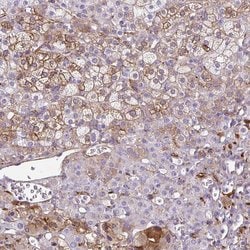

Invitrogen™ NGB Polyclonal Antibody

Brand: Invitrogen™ PA563594

| Immunohistochemistry (Paraffin) | |